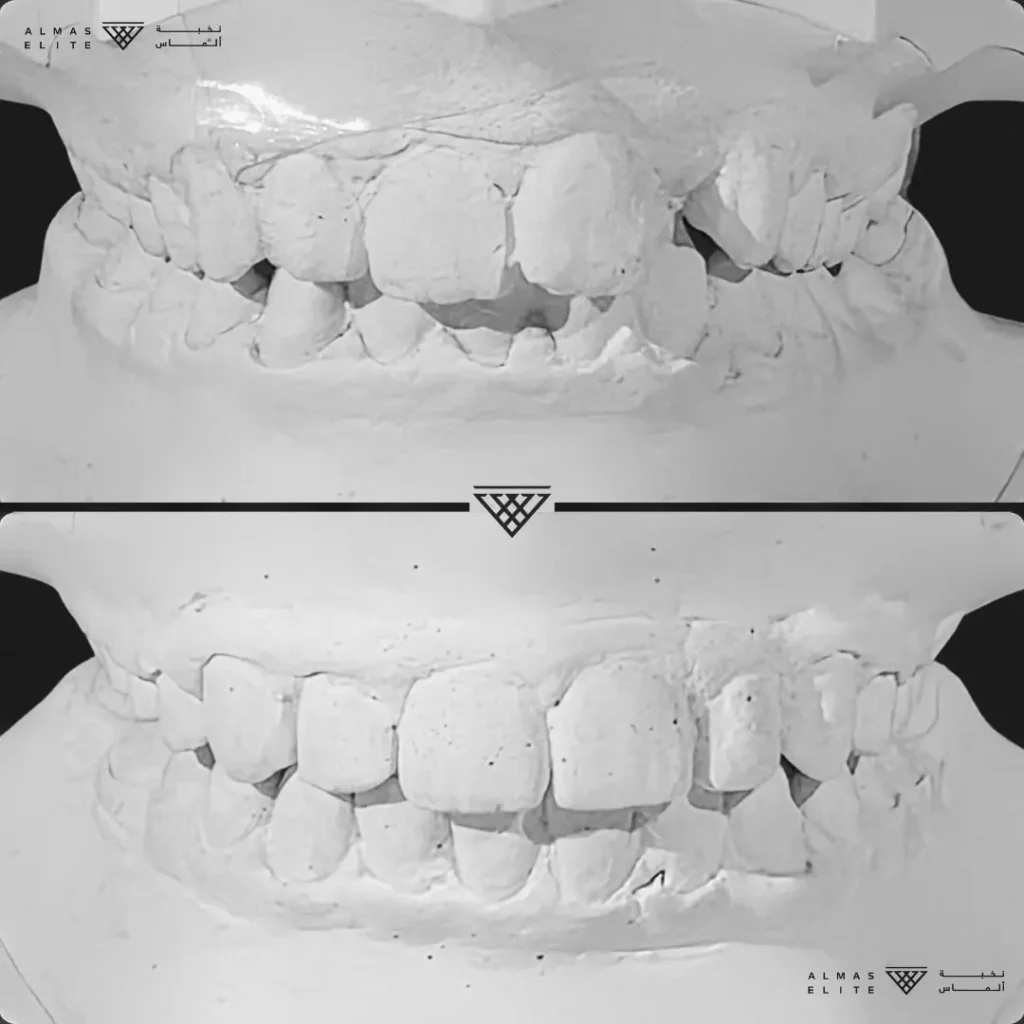

- تشخيص دقيق يشمل الأشعة والتحليل الرقمي للأسنان والفكين.

٢) التقييم والتشخيص الشامل

يشمل صور الأشعة والتحليل الرقمي للأسنان والفكين للوصول إلى تشخيص دقيق.

٣) وضع خطة علاجية مخصصة

تتضمن نوع الجهاز الأنسب، المدة المتوقعة، وتكلفة العلاج، مع شرح واضح لما يمكن توقعه أثناء رحلة التقويم.